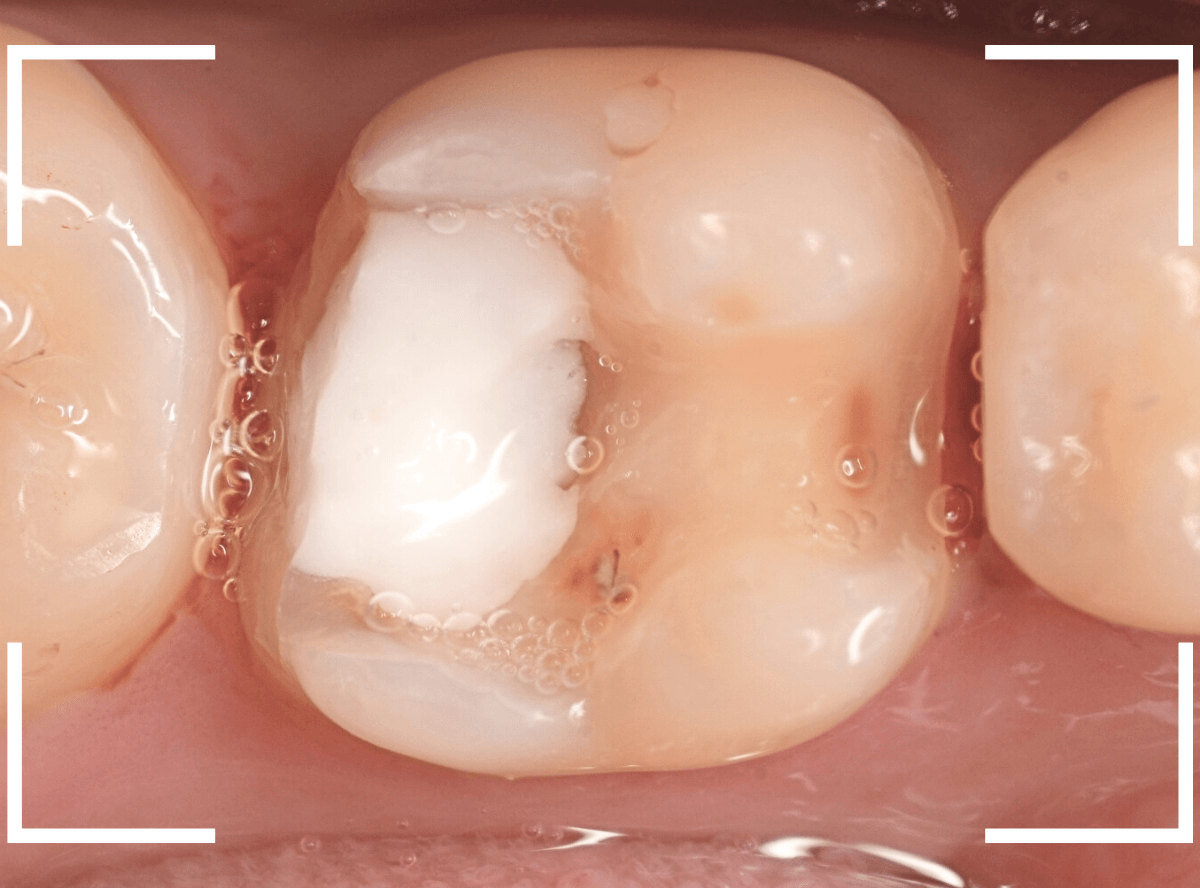

虫歯を治療して、セメントで歯を削った部分を封鎖した後、再修復を検討中で、半年以上来院されなかった患者さんです。

虫歯を治療して、セメントで封鎖した状態というのは、家でいえば、しっかりした屋根がない状態です。

今回は、セメントの一部がはがれる程度で済んでいましたが、虫歯が再発し、再治療、最終修復物の変更の可能性も出てきます。

皆さんも治療は中断せずに最後まで通院するようにしてくださいね。

治療再開後、セラミックの最終修復を希望されましたので、歯をトリミングし、型取りします。